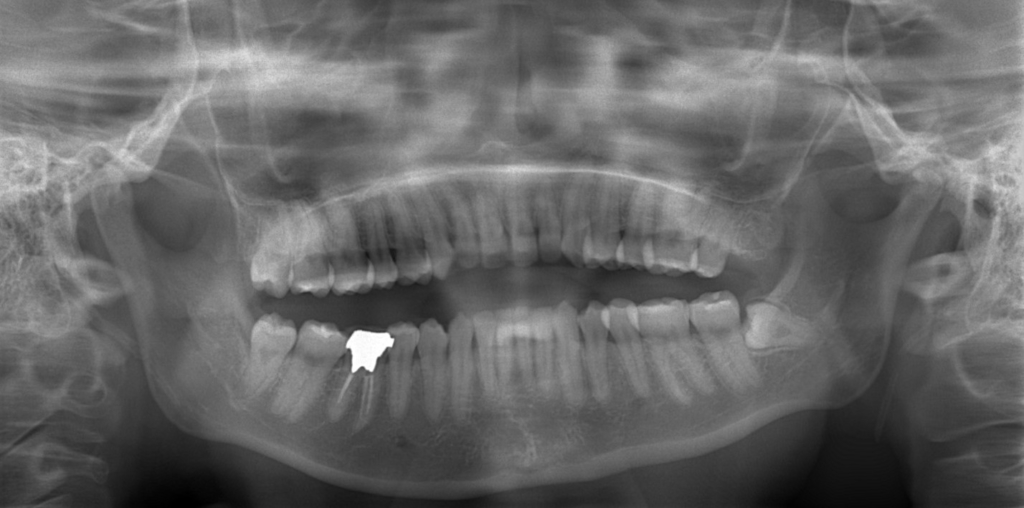

レントゲン写真でも比較してみましょう

左側が矯正治療前、右側が矯正治療後